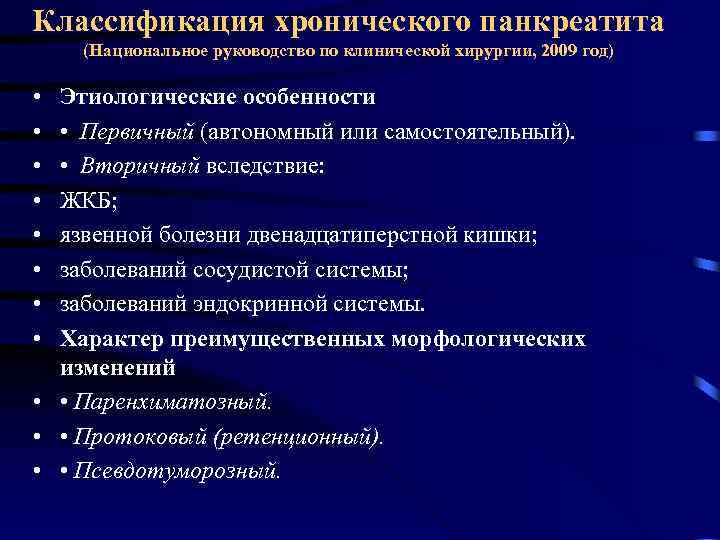

Классификация хронического панкреатита (Национальное руководство по клинической хирургии, 2009 год) • • Этиологические особенности • Первичный (автономный или самостоятельный). • Вторичный вследствие: ЖКБ; язвенной болезни двенадцатиперстной кишки; заболеваний сосудистой системы; заболеваний эндокринной системы. Характер преимущественных морфологических изменений • • Паренхиматозный. • • Протоковый (ретенционный). • • Псевдотуморозный.